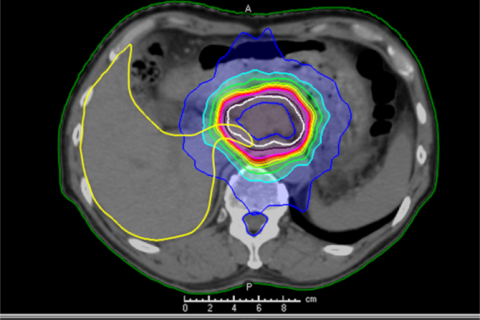

肝臓がんに対する定位照射

少数個転移(オリゴ転移)に対する定位放射線治療(ピンポイント照射)について

がんが他の部位に転移している場合でも、転移の数が限られている状態を「少数個転移(オリゴ転移)」と呼びます。 このような状態では、転移した病変一つひとつを狙って治療することで、病状の進行を抑えることが期待できる場合があります。

少数個転移に対する治療法の一つが、定位放射線治療(ピンポイント照射)です。

定位放射線治療は、病変の位置を正確に捉え、周囲の正常な組織への影響をできるだけ抑えながら、狙った部位に集中的に放射線を照射する高精度な治療法です。

当院では、少数個転移に対する定位放射線治療を、4回から20回に分けて行っています。

転移の部位や、周囲に副作用が起こりやすい臓器が近い場合には、照射回数を増やして1回あたりの放射線量を抑え、安全性を高める工夫を行っています。